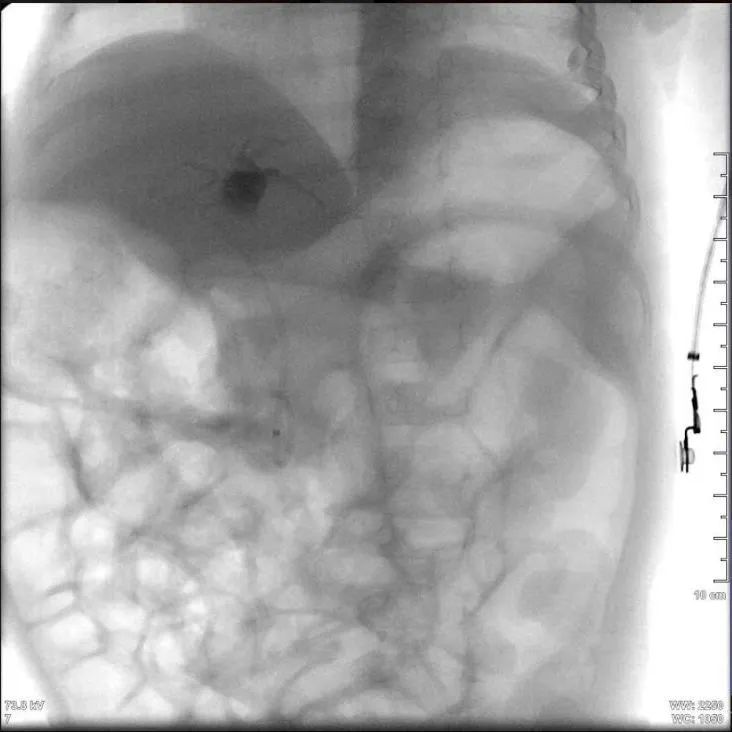

图片

支架置入后造影

术后奇迹立现:持续攀升的胆红素迅速回落,受损肝功能各项指标稳步回归正常范围。手术的成功也重启了患儿抗癌治疗的关键通道。